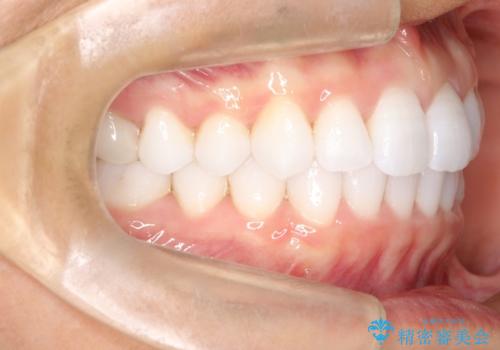

気になる前歯の歯並びをインビザラインで矯正

- 前歯の傾きと、ガタガタが気になるとのことで来院されました。

アスリートの方でしたので、競技に支障が少ないインビザラインで治療することとなりました。

前歯の傾きや高さをシミュレーションで患者様と確認しながら、歯並びを仕上げていきました。

遠方での合宿などで長期に来院できない場合も、インビザラインなら治療が可能となります。